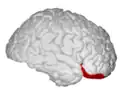

Orbitofrontal cortex

The orbitofrontal cortex (OFC) is a prefrontal cortex region in the frontal lobes of the brain which is involved in the cognitive process of decision-making. In non-human primates it consists of the association cortex areas Brodmann area 11, 12 and 13; in humans it consists of Brodmann area 10, 11 and 47.[1]

The OFC is functionally related to the ventromedial prefrontal cortex.[2] Therefore, the region is distinguished due to the distinct neural connections and the distinct functions it performs.[3] It is defined as the part of the prefrontal cortex that receives projections from the medial dorsal nucleus of the thalamus, and is thought to represent emotion, taste, smell and reward in decision-making.[4][5][6][7][8][9][10][11] It gets its name from its position immediately above the orbits in which the eyes are located. Considerable individual variability has been found in the OFC of humans.[12] A related area is found in rodents.[13]